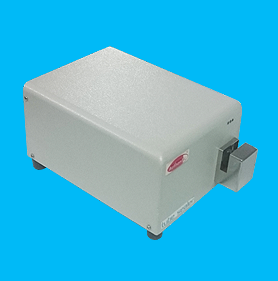

BLOOD TUBE SEALER

Sealing time : 0.6 to 2 Second.

Tube diameter : 2 to 8 mm with wall thickness of 0.75 mm.

Dimension : 300 (L) x 175 (B) x 150 (H) in mm .